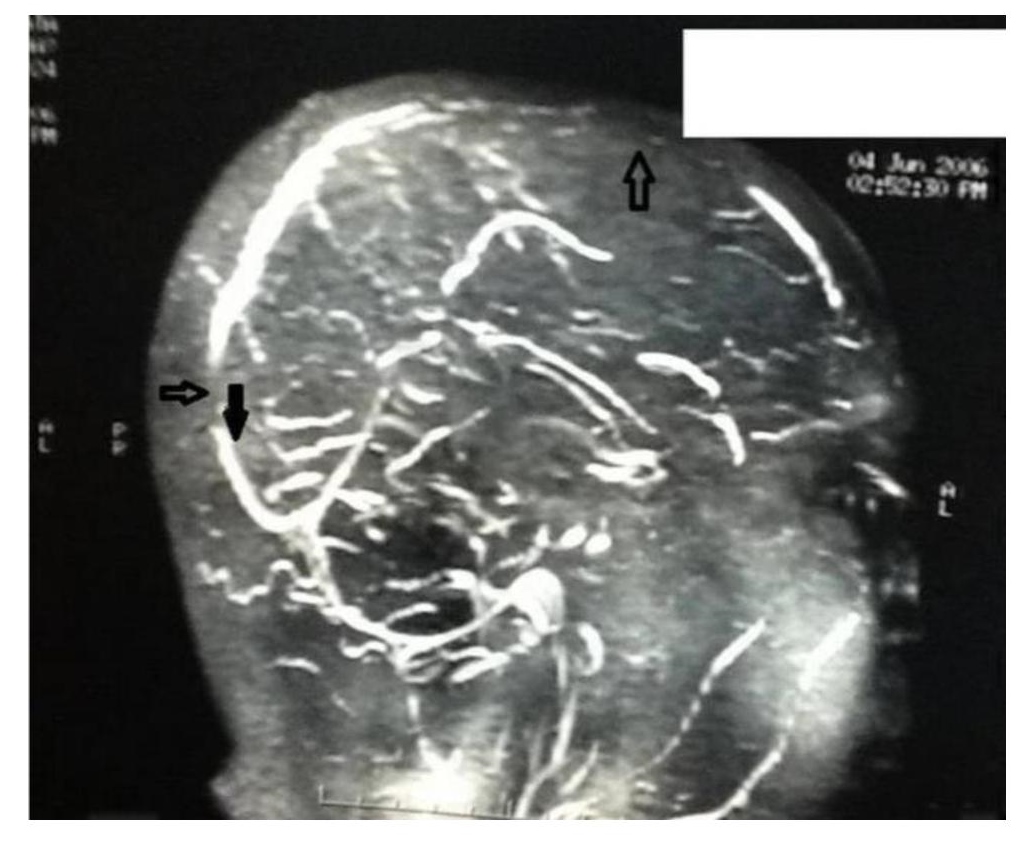

The patient's hemoglobin, total leucocyte count, ESR and platelet count were within normal ranges (Table 1). Additional laboratory studies showed normal blood chemistry results including electrolytes, renal and liver function tests, FBS and HbA1c (Table 1). The 2D echocardiogram was also normal. His lipid profile showed grossly elevated triglyceride levels of 838 mg/dl with LDL-cholesterol of 120mg/dl and HDL-cholesterol of 48 mg/dl (Table 2). Cranial computed tomography scan was normal, but magnetic resonance imaging with magnetic resonance angiography of the brain showed thrombosis of the superior sagittal sinus (Figure 1).

Figure 1. magnetic resonance imaging (MRI) with magnetic resonance angiography (MRA) brain. The arrow showing thrombosis of superior sagittal sinus thrombosis.